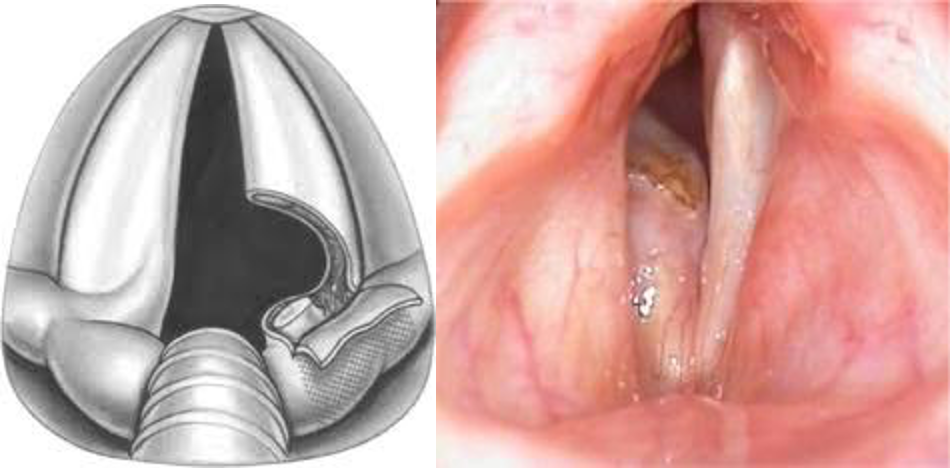

Arytenoidectomy

abduction paralysis lateralization or arytenoidectomy Z OSPE